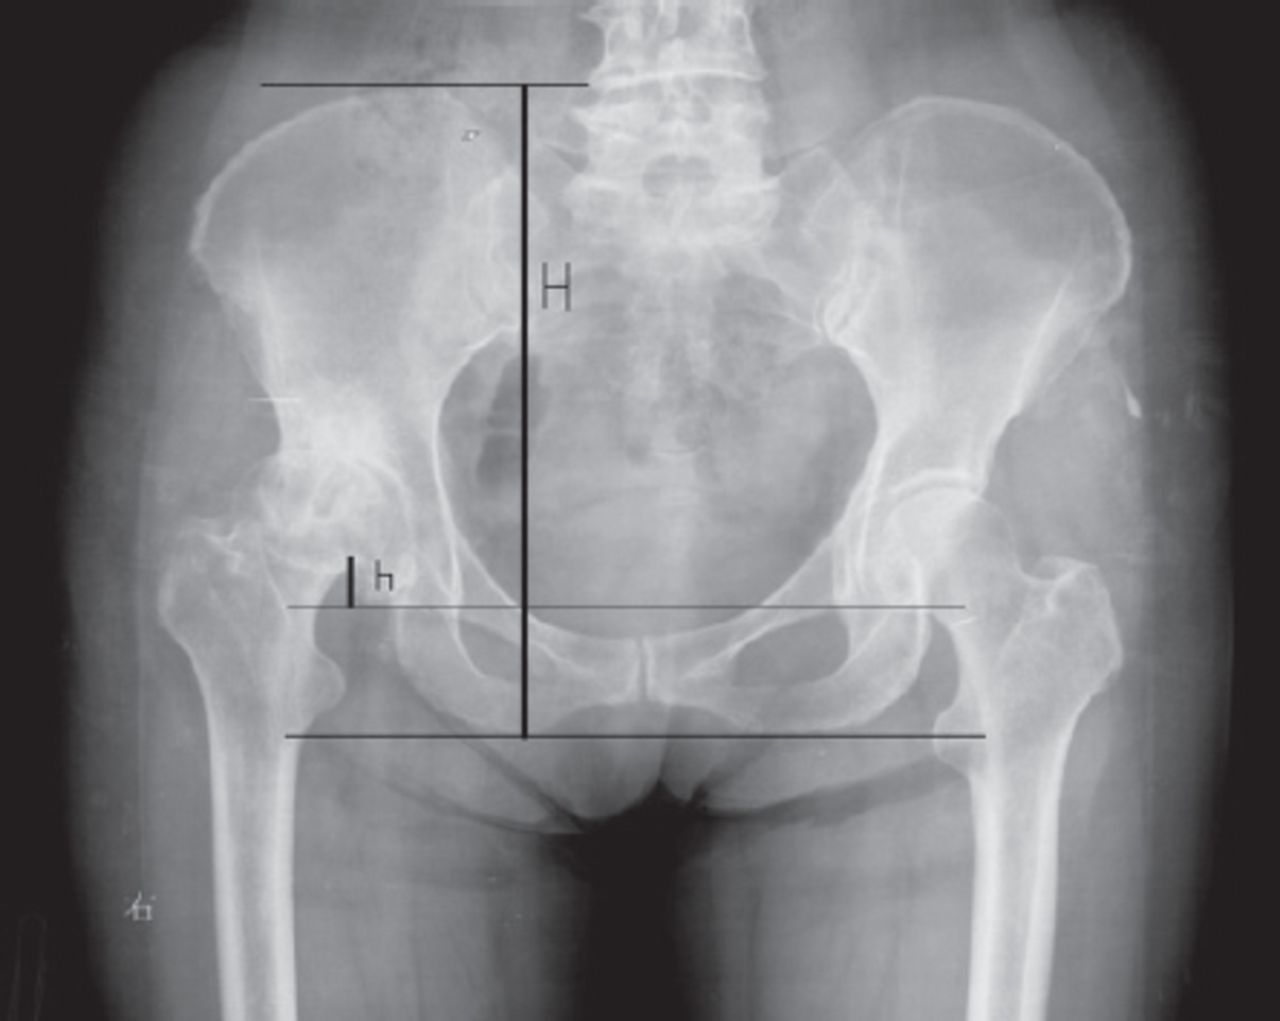

لگن نامتقارن به وضعیتی گفته می شود که در آن دو سمت استخوان لگن در یک راستا و سطح قرار ندارند و یکی از سمت ها بالاتر، پایین تر یا جلوتر از سمت دیگر قرار می گیرد. این عدم تعادل می تواند به صورت تیلت قدامی، تیلت خلفی یا انحراف جانبی بروز کند و در معاینه بالینی به صورت تفاوت ارتفاع خار خاصره ای قابل مشاهده است.

در نوع دیگر، تیلت لگن به صورت خلفی است که با صاف شدن قوس کمری و کشیدگی عضلات پشت ران همراه است. نوع سوم، انحراف جانبی لگن است که در آن یک سمت لگن بالاتر از سمت دیگر قرار می گیرد و ممکن است با اختلاف طول اندام یا اسپاسم عضلات یک طرفه مرتبط باشد. تشخیص دقیق این انواع در ارزیابی تخصصی فیزیوتراپی انجام می شود.

در تیلت جانبی لگن، یک سمت استخوان لگن بالاتر از سمت دیگر قرار می گیرد و در نمای ایستاده، عدم تقارن به صورت واضح قابل مشاهده است. این نوع از لگن نامتقارن معمولا با انتقال وزن بیشتر به یک پا همراه است و ممکن است فرد احساس کند یکی از پاها کوتاه تر از دیگری است. در بسیاری از موارد، این وضعیت به صورت تدریجی ایجاد شده و تا زمان بروز درد مورد توجه قرار نمی گیرد.

در فیزیوتراپی لگن، ارزیابی دقیق وضعیت ایستادن، راه رفتن و دامنه حرکتی مفاصل انجام می شود. متخصص با لمس و مشاهده، تفاوت ارتفاع لگن و چرخش آن را بررسی می کند. در صورت نیاز، تست های عملکردی برای ارزیابی قدرت و انعطاف پذیری عضلات انجام می شود.

گاهی برای بررسی دقیق تر از تصویربرداری مانند رادیوگرافی استفاده می شود، اما در بسیاری از موارد معاینه بالینی دقیق کافی است. هدف از تشخیص، شناسایی منبع اصلی اختلال و طراحی برنامه درمانی اختصاصی برای هر فرد است.